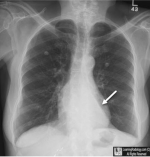

| D | Diaphragm | • shape may be flat with COPD,tension pneumothorax •R higher than L • look for free gas below |

| E | Effusions Extra-thoracic | • costo-phrenic angles for sharpness |